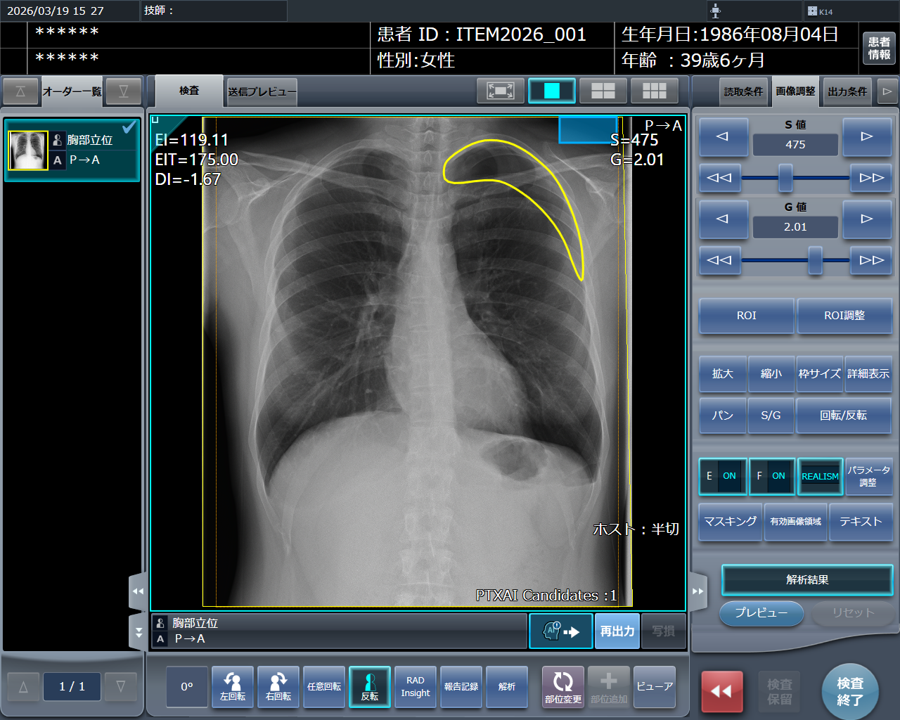

コンピューターのスクリーンショット

「CXR Finding-i 気胸検出タイプ」により解析された気胸の検出領域を表示

■気胸検出機能(「CXR Finding-i 気胸検出タイプ」との連携)

気胸の診断支援を行うプログラム「CXR Finding-i 気胸検出タイプ」と連携することで、ガイドラインにおいて一般撮影で診療放射線技師が発見した場合に報告すべきSTAT画像所見の一つに挙げられている気胸の候補を高精度で検出することができます。